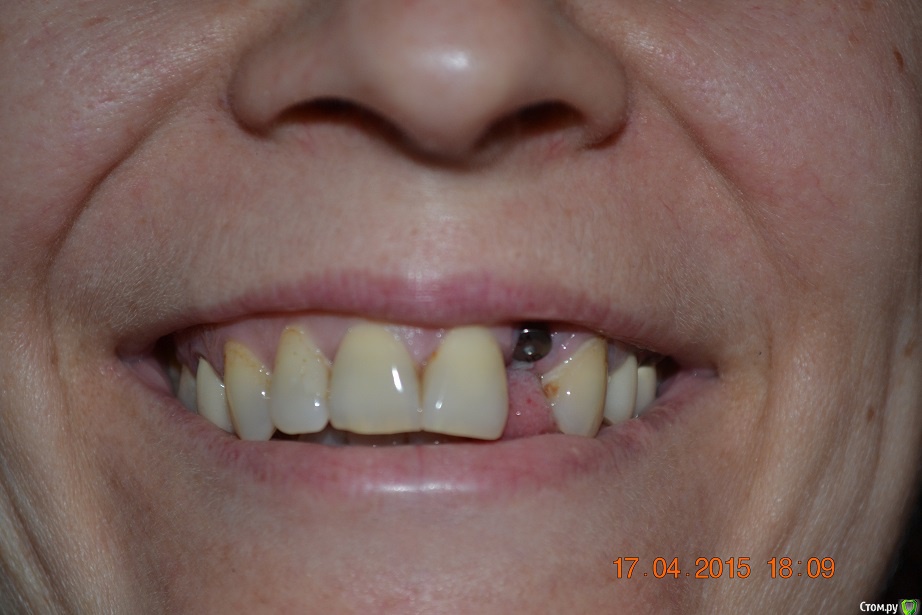

red_butler Опубликовано 17 апреля, 2015 Поделиться Опубликовано 17 апреля, 2015 спасибо, а кто проводит такие операции? сам хирург-имплантолог который ставил имплант? почему сложилась такая ситуация с десной? это моя вина или из-за слишком высокого уровня установки импланта? спасибо.делает хирург который это умеет, да имплант поставлен слегка выше. Покажите фото своей улыбки Ссылка на комментарий

nat-man Опубликовано 17 апреля, 2015 Автор Поделиться Опубликовано 17 апреля, 2015 вот как-то так Ссылка на комментарий

red_butler Опубликовано 17 апреля, 2015 Поделиться Опубликовано 17 апреля, 2015 требуется пластика десны Ссылка на комментарий